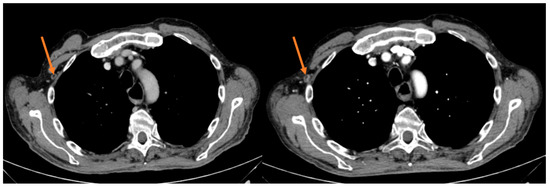

After the first tumor evaluation at 6 weeks, out of 8 patients 1 exhibited a partial response (PR) (12.5%) and 1 stable disease (SD) (12.5%), whereas 6 patients (75%) had a progressive disease (PD), accounting for a 25% DCR (2/8). Notwithstanding the measurable DCR, the primary end point of a 12-week PFS rate was not met since after 12 weeks of treatment only 1 patient achieved SD (Figure 2).

Figure 2.

Intercostal lesion before and after 12 weeks of treatment in the responder patient.

Median PFS was 2.1 months (95% CI 1.10–3.10), with the longest PFS duration (5.0 months) measured in the patient achieving a PR. During the median follow-up of 28.3 months, the median OS was 8.2 months (95% CI 4.86–11.54); two patients are still alive and are currently receiving a third-line chemotherapeutic treatment (Table 3).